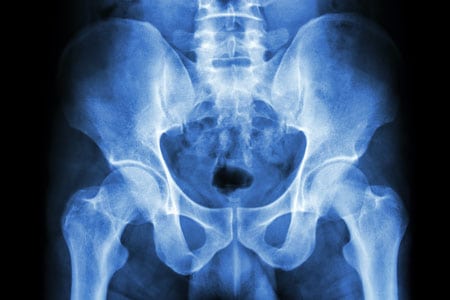

Reconstructive urology can also help repair traumatic injuries to the kidney, ureter, bladder, and genitals. Traumatic injuries are often associated with pelvic fractures that can happen as a result of things like motor vehicle accidents or falls and can frequently lead to scar tissue formation in the urethra.